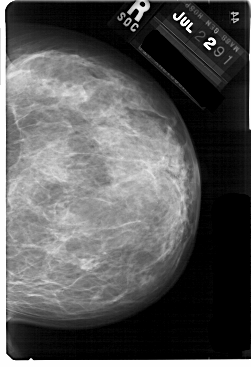

A_1757_1.RIGHT_MLO

RIGHT_CC LINES 5491 PIXELS_PER_LINE 3751 BITS_PER_PIXEL 12 RESOLUTION 43.5 NON_OVERLAY

RIGHT_MLO LINES 5491 PIXELS_PER_LINE 4021 BITS_PER_PIXEL 12 RESOLUTION 43.5 NON_OVERLAY